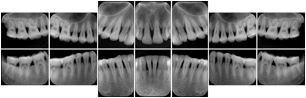

Intra-oral radiography typically involves acquisition of multiple images of various parts of the dentition. Many digital radiographic systems offer customized templates that are used for displaying the images in a study on the screen. These templates may also be referred to as mounts or view sets. The Structured Display Object represents a standard method of encoding and exchanging the layout and intended display of Structured Displays. A structured display object created in this manner could be stored with a study and exchanged with images to allow for complete reproduction of the original exam.

1. A patient visits a General Dentist where a Full Mouth Series Exam with 18 images is acquired. The dentist observes severe bone loss and refers the patient to a Periodontist. The 18 images from the Full Mouth Series along with a Structured Display are copied to a DICOM Interchange CD and sent with the patient to see the specialist. The Periodontist uses the CD to open the exam in his Dental Radiographic Software and consults via phone with the General Dentist. Both are able to observe the same exam showing the images on each user's display using the exact same layout.

Intra-oral Full Mouth Series Structured Display

Figure OO-1. Intra-oral Full Mouth Series Structured Display